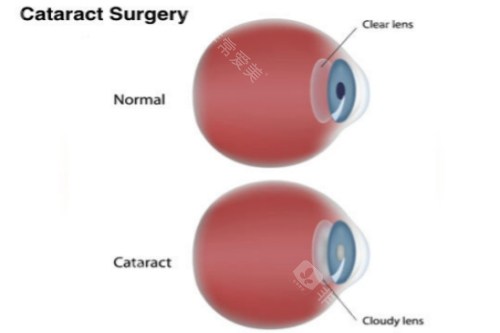

白内障正规开展了多种白内障手术,包括超声乳化白内障吸除术等,手术技术成熟,术后结果良好。